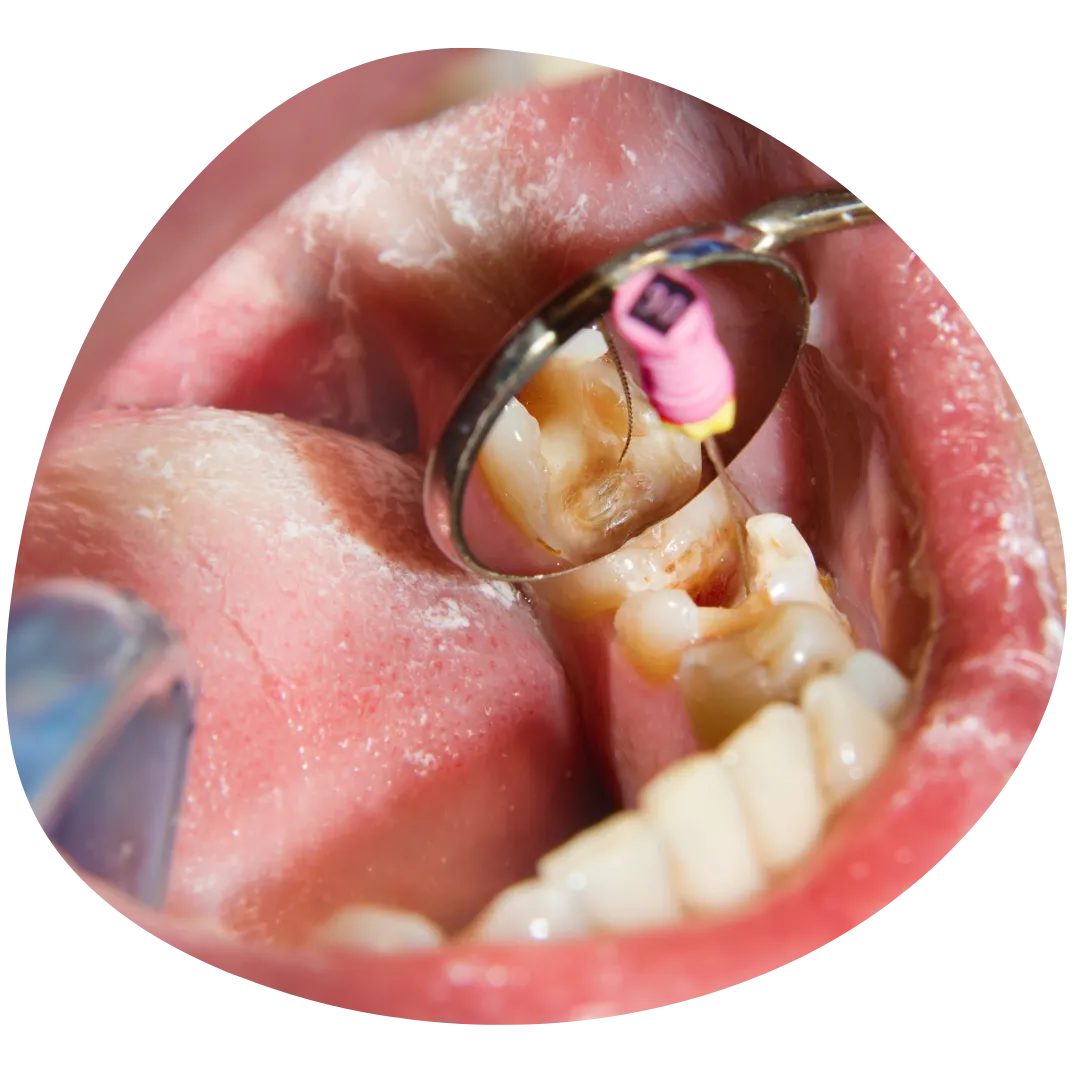

Kako endodoncija može spasiti Vaš zub?

Endodoncija, poznata i kao liječenje kanala korijena, ključna je za spašavanje zuba koji je ozbiljno oštećen ili zaražen. U Dental Studio dr. Jusić, pažljivo uklanjamo inficirano tkivo iz unutrašnjosti zuba, čistimo kanale i ispunjavamo ih biokompatibilnim materijalom. Ovaj postupak ne samo da eliminira bol i infekciju, već i sprječava potrebu za vađenjem zuba, omogućavajući Vam da zadržite prirodan osmijeh i funkcionalnost zuba.

Koje su prednosti endodontske terapije u Dental Studio dr. Jusić?

Endodontska terapija u Dental Studio dr. Jusić pruža brojne prednosti, uključujući očuvanje Vaših prirodnih zuba i prevenciju daljnjih dentalnih problema. Dr. Jusić koristi najnoviju tehnologiju i moderne metode kako bi osigurali precizno i bezbolno liječenje. Pored toga, individualni pristup svakom pacijentu omogućava nam da prilagodimo terapiju vašim specifičnim potrebama, što rezultira bržim oporavkom i dugotrajnim rezultatima.